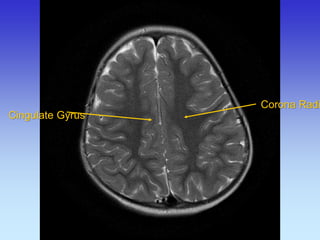

Cingulate Gyrus

Corona Radiata